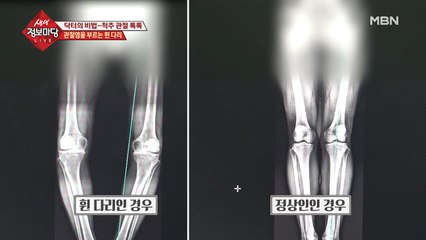

내 다리가 못생긴 이유…! 토실토실 [지방형 다리]